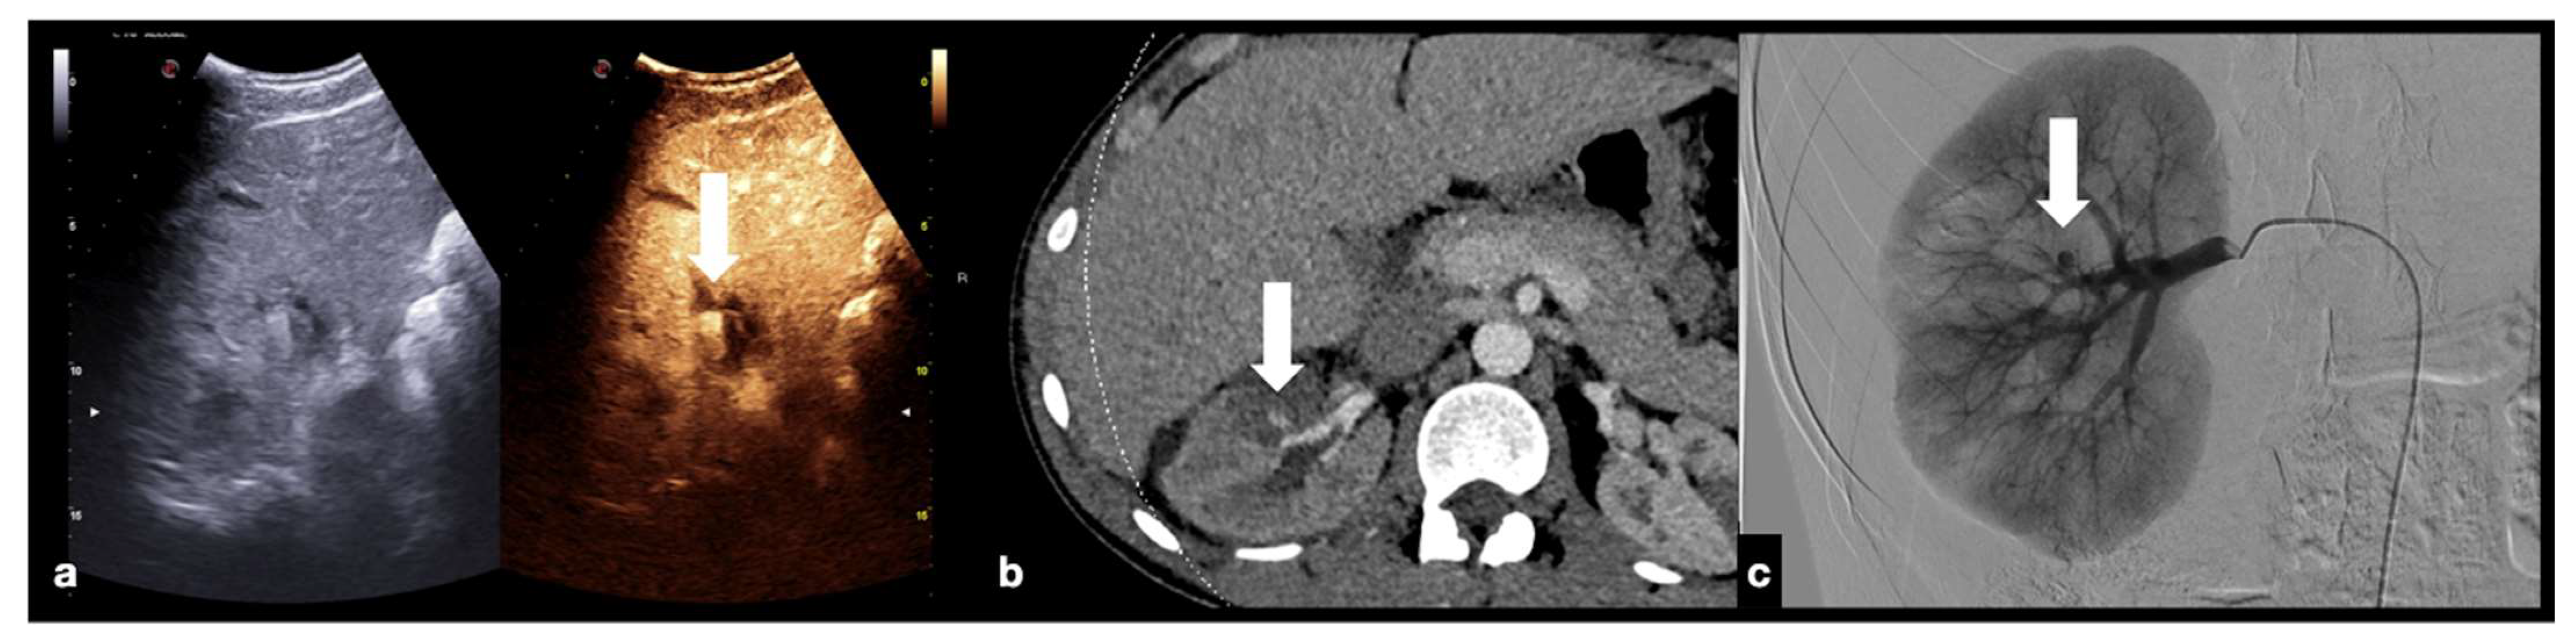

Figure 20.

CEUS (a) of a 23−year-old man referring to the emergency department for direct blunt trauma to the right flank showed the presence of a small pseudoaneurysm (white arrow) inside the contusion area of the right kidney; the diagnosis was then confirmed at the axial arterial phase contrast-enhanced CT scan (b), as well as at angiography performed for treatment purposes (c).